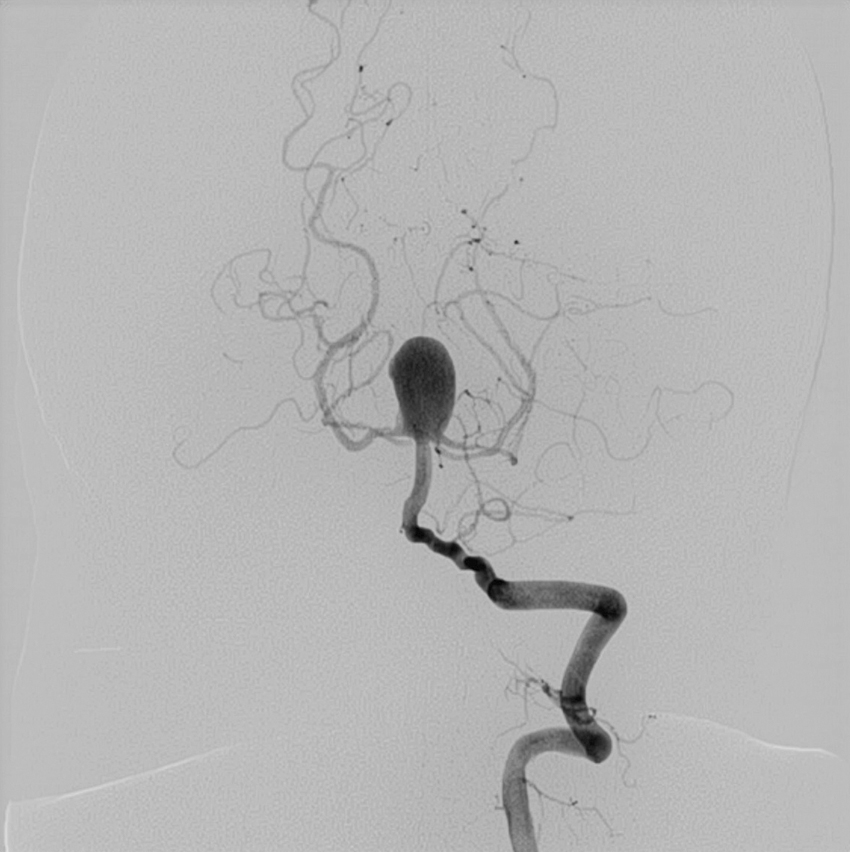

1) 혈관내 치료(Endovascular Treatment): 두개골을 열지 않고 바로 동맥 혈관 내부로 카테타를 넣고, 미세 카테타를 뇌동맥류로 삽입한 후 백금실(코일)을 충전하는 치료 방법이다. 코일 색전술로 알려져 있으며, 파열 뇌동맥류, 즉 지주막하 출혈의 경우 첫 번째로 선택되는 치료방법이다.

기저동맥 첨부 뇌동맥류

기저동맥 첨부 뇌동맥류 코일색전 후